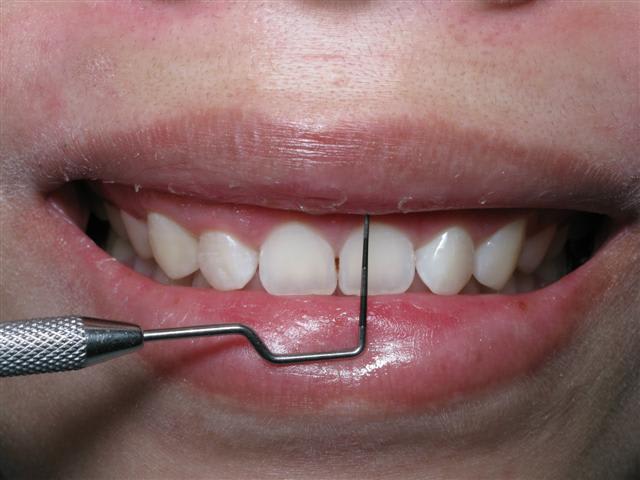

Photo d'un cas similaire

Petite question pour le cas de Ceramik justement:

pourquoi pas de d'allongement de couronne dans ton cas qui présente les mêmes caractéristiques: émail recouvert ( après ortho peut-être) et gummy smile ?

Qui te dit que ça n'a pas été fait après ?

Une combinaison de techniques était nécessaire dans ce cas.

Non seulement un ''lip-tack''

pas de travail osseux.

Le repositionnement labial n'est qu'un raccourcissement vestibulaire comme dans le cas clinique qui suit.

Simple, peu de suite post op et un résultat convenable.